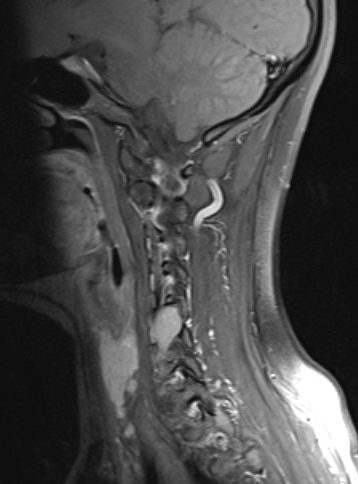

Paciente que presenta dolor braquial izquierdo moderado, territorio C6, predominio nocturno, de >6 meses de evolución. Según su origen en relación a la raíz y su tamaño, puede clasificarse en distintos subtipos.

Imagen sagital con ocupación de foramen.

Tumoración en espacio extracanal y extraforaminal, que capta gadolinio de manera homogénea y que se encuentra adherida a arteria vertebral izquierda.